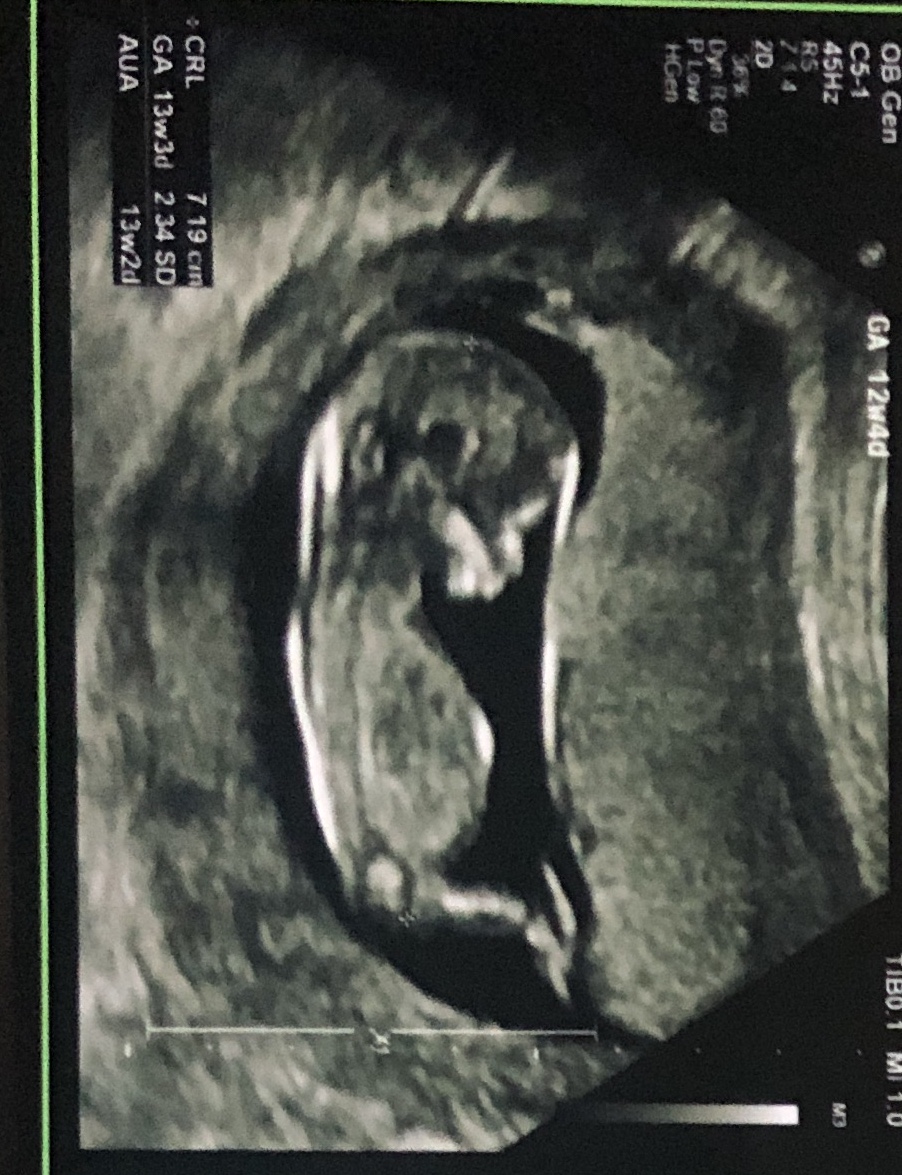

Little anxious to find our little one’s gender. Attached are ultrasound images at 12+4 days (age as per CRL dating)Attachment 42397Attachment 42398Attachment 42397Attachment 42398